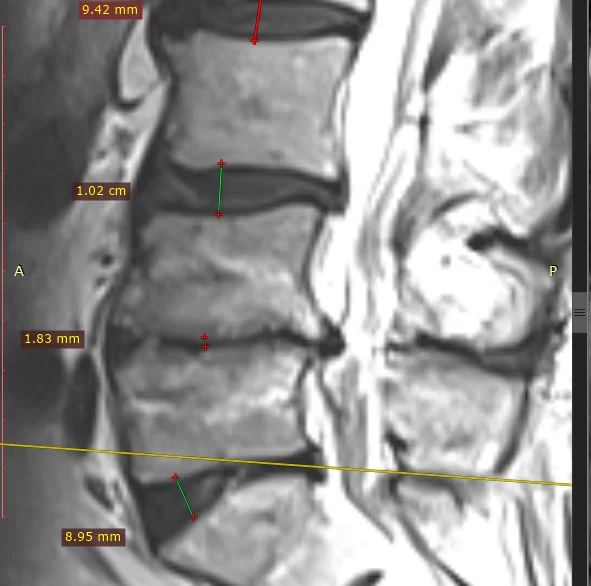

Acest bărbat în vârstă de 64 de ani s-a prezentat la un consult cu dureri severe de spate. Deși a urmat nenumărate tratamente nonchirurgicale, starea lui a continuat să se agraveze și durerile să se accentueze. După RMN-ul din 12 august 2021 în care se poate observa clar cât de acentuat este gradul de degenerare, am luat decizia de a interveni din lateral întrucât gradul de instabilitate era foarte mare. El a avut o îmbunătățire a simptomelor într-un timp scurt, a reușit să își reia o parte din activitățile fizice zilnice care l-au ajutat să își revină și să se simtă alt om.